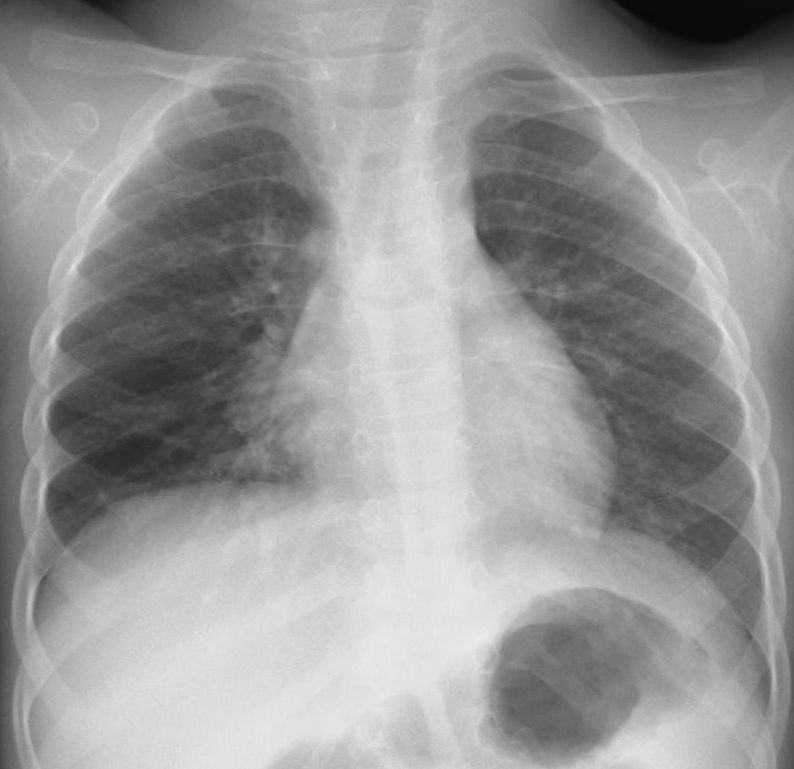

インフルエンザA肺炎50歳